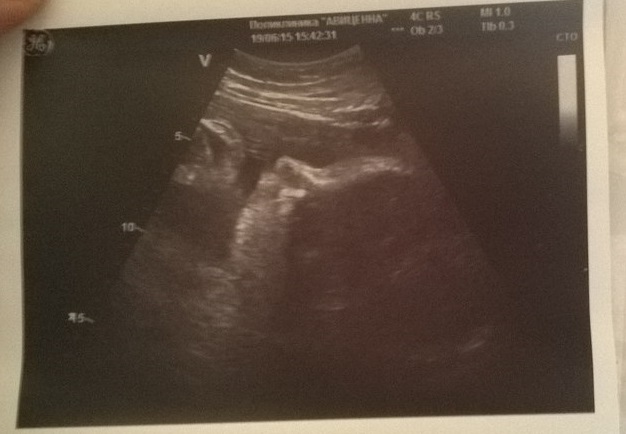

40 недель, узи

УЗИ, КТГ, доплерВот не сидится мне на месте, уже в роддом пора, а я на узи пошла. Ставят крупный плод, очень хотелось оценить ситуацию...посмотреть насколько мы выросли с третьего скрининга.

ПДР 22 июня) 40 неделек нам по узи. Нос сказали в меня)))щекастик мой чувствует себя замечательно, правильно лежит,ждет своего часа, чувствует себя хорошо. Предполагаемый вес 3800 +- 500г (погрешность). Ну в общем пишут, что мы крыпненькие. Узист сказала, таз хороший - рожу)...в общем мы на старте... (наше фото с узи под катом)